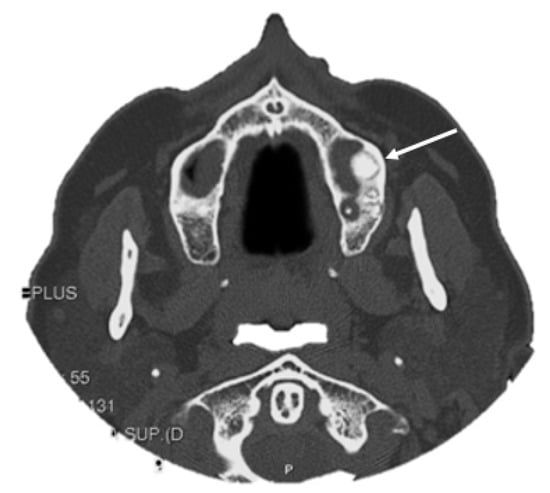

4. Imaging